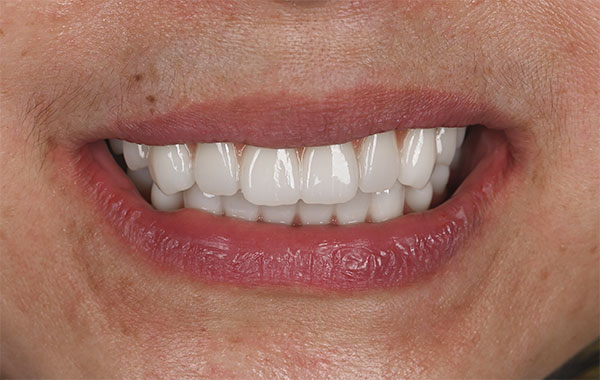

術後の正面観とスマイル時